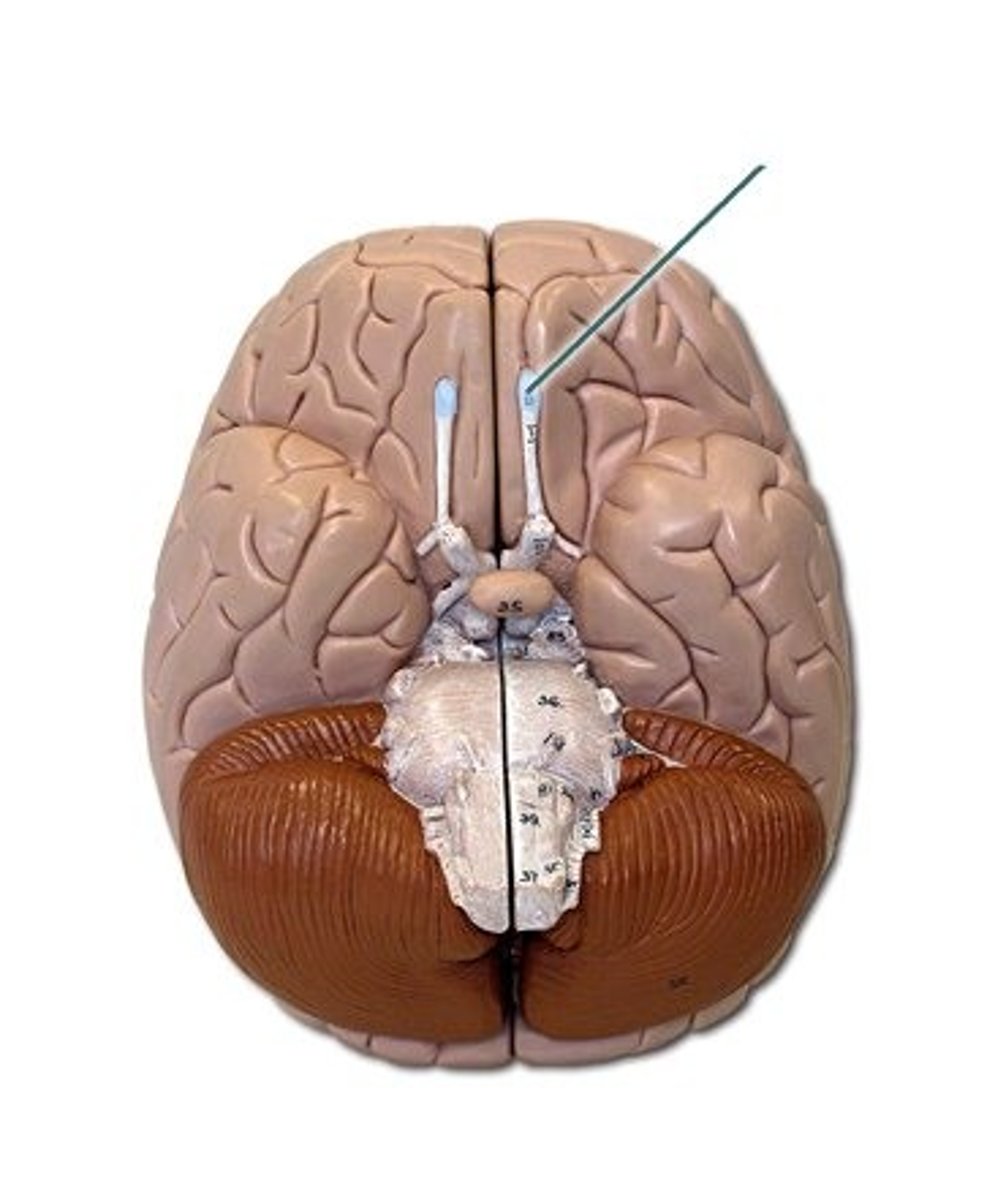

optic nerve (CN II)

Sensory cranial nerve related to vision

optic chiasm

point at which optic nerve fibers cross in the brain

optic tracts

the continuation of the optic nerve fibers beyond the optic chiasma